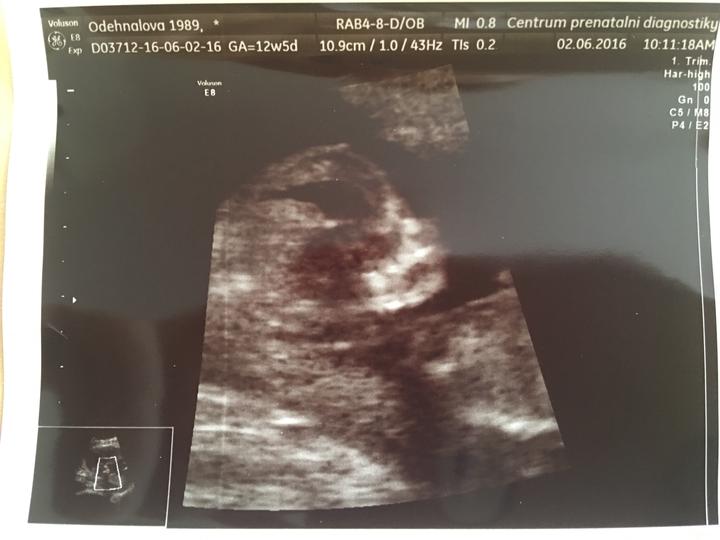

Dnešní kontrola za náma a všechno v pořádku!! Jsme 20tt+1 a v úterý jdeme na druhý screening 💜